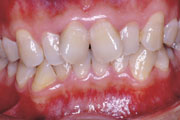

一般矯正の症例

症例1:乱杭歯(叢生)